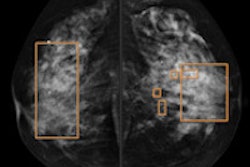

A 68-year-old asymptomatic woman underwent routine mammographic screening (above). A subtle small spiculated mass was correctly detected by CAD in the upper-outer quadrant of the right breast, best seen on the mediolateral oblique (MLO) view (below). Percutaneous biopsy and subsequent surgical excision confirmed a 10-mm well-differentiated, lymph-node-negative invasive ductal cancer in the right breast [pT1b pN0 (sn) G1], which had an excellent prognosis due to its early detection through mammography screening. Images courtesy of Dr. Ulrich Bick.Results from the European breast cancer diagnosis project, HAMAM, which uses CAD in a more patient-tailored approach, are promising. The project integrates MRI, mammography, and ultrasound with risk factors such as age and gene mutation carrier information. Some risk factors, such as breast density and composition, can even be extracted and factored into CAD's findings.